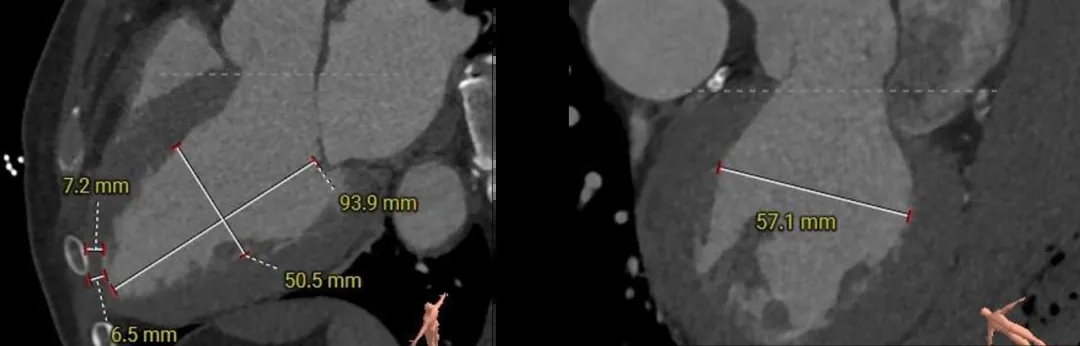

三叶式主动脉瓣,瓣叶轻微增厚;瓣环周长折算直径29.7mm,LVOT32.4mm。

左冠开口高度约为15.5mm,右冠开口高度约为18.9mm,双侧冠脉堵塞风险较低。

左室增大,瓣环夹角56°,非横位心。

主动脉根部测量

Annulus:29.7mm

LVOT:32.4mm

三叶瓣

SOV:40*39.1*38.2mm

STJ:37.9mm

AAO:43mm

瓣上结构测量

瓣上2mm:28.3mm

瓣上4mm:29.2mm

瓣上6mm:29.8mm

瓣上8mm:31.3mm

瓣上10mm:32.4mm

瓣上12mm:32.6mm

冠脉风险评估

外周入路评估